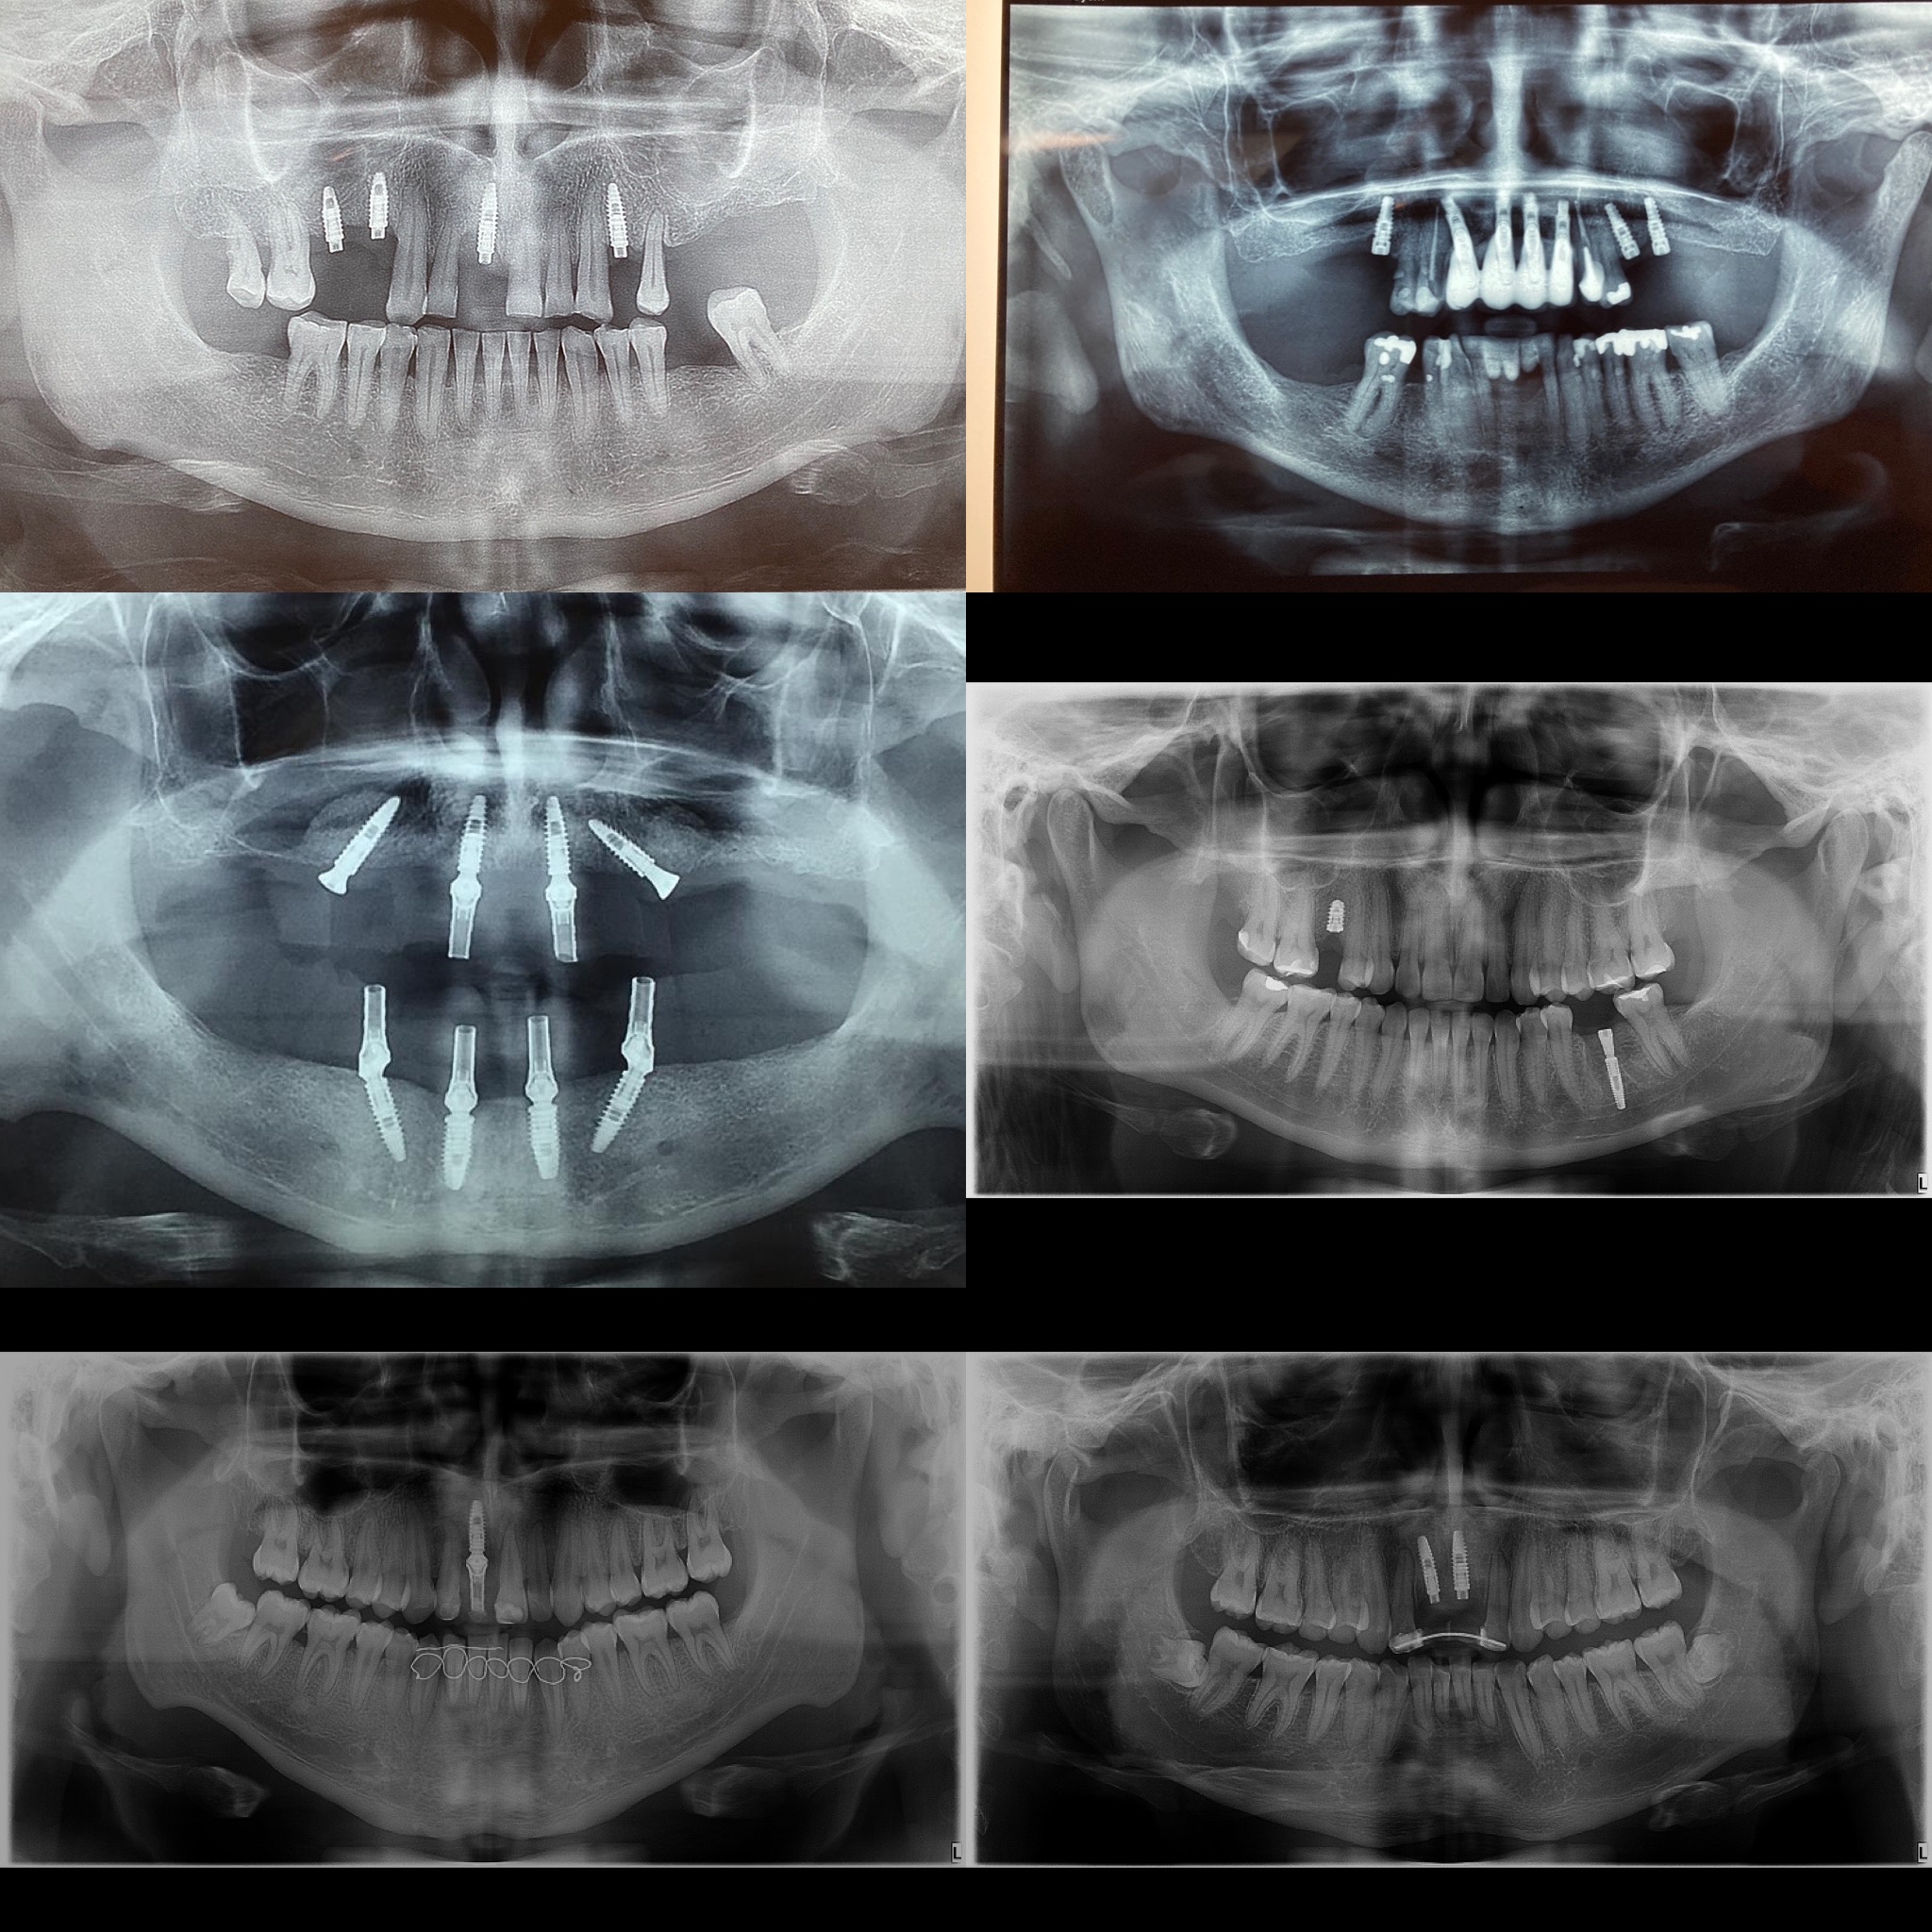

Implantes Cigomáticos y Mandibulares “all on four”

Los implantes cigomáticos son una alternativa a los implantes dentales convencionales para pacientes que no tienen suficiente hueso maxilar o que lo han perdido por completo. Se colocan en el hueso cigomático o malar, que es la parte inferior del pómulo, y son más largos que los implantes dentales tradicionales, con una longitud de entre 30 y 60 milímetros. Los implantes cigomáticos son una opción para pacientes que: Los implantes cigomáticos permiten: El procedimiento de colocación de implantes cigomáticos es mínimamente invasivo y no deja cicatrices externas en la cara.

Implantes dentarios

Los implantes dentarios son una opción de tratamiento utilizada para reemplazar dientes perdidos o dañados de manera permanente. Están compuestos por una estructura de titanio o material similar que se inserta quirúrgicamente en el hueso de la mandíbula, donde actúa como una raíz artificial sobre la cual se coloca una corona, puente o prótesis dental. Componentes principales de un implante dental: Ventajas de los implantes dentarios: Proceso de colocación de un implante dental: Candidatos ideales para implantes: Los candidatos ideales son personas saludables, con suficiente hueso en la mandíbula y sin infecciones orales graves. Las personas con enfermedades crónicas, como diabetes no controlada, o problemas de encías pueden necesitar un tratamiento especial antes de considerar los implantes.